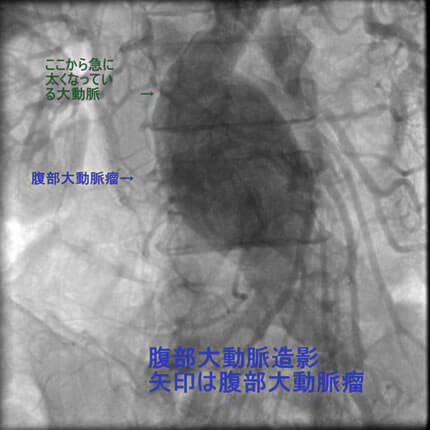

図2-4 腹部大動脈造影

また、動脈硬化は冠動脈だけに生じる訳ではないことも示したいと思います。冠動脈に病変がある方は他の動脈にも強い動脈硬化を認めることが多いのです。具体的には腹部大動脈瘤、胸部大動脈瘤、脳梗塞、脳出血、下肢動脈閉塞などを合併します。逆にこれらの病気が見つかってそれから冠動脈疾患が見つかることも結構あります。血管は三次元構造なので色々な方向から撮影して血管形態を確かめます。同じ血管を左右上下や斜め方向から撮影します。

今回お示しする三人の患者さんは全て冠動脈疾患と動脈瘤を合併する方です。